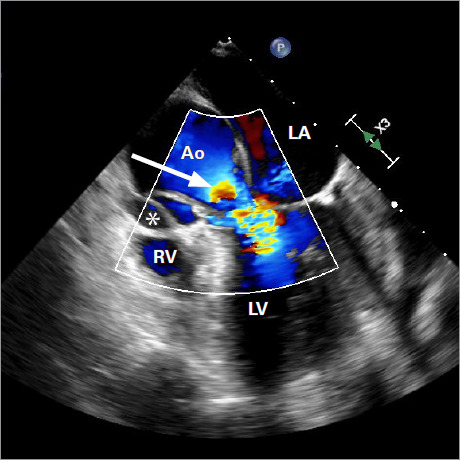

这个新颖的病例记录了一名 75 岁女性患者在修复升主动脉瘤后,成功使用经导管主动脉瓣植入术治疗主动脉根部夹层引起的严重主动脉瓣关闭不全。在她出现充血性心力衰竭症状后,检查发现了新的严重主动脉瓣关闭不全和急性主动脉夹层。考虑到再次手术的风险过高,患者接受了 27 毫米的 Portico(St Jude Medical)自扩张人工主动脉瓣手术,结果临床症状大为改善,且未出现手术并发症。该病例凸显了经导管主动脉瓣植入术在治疗复杂主动脉疾病方面的多功能性,并强调了多学科评估和谨慎选择人工瓣膜的关键作用。

This novel case documents the successful use of transcatheter aortic valve implantation to treat severe aortic insufficiency arising from aortic root dissection following the repair of an ascending aortic aneurysm in a 75-year-old female patient. After she presented with symptoms of congestive heart failure, investigation revealed new severe aortic insufficiency and an acute aortic dissection. Given the prohibitive risks of reoperation, a self-expanding 27-mm Portico (St Jude Medical) prosthetic aortic valve was deployed, resulting in substantial clinical improvement without procedural complications. This case highlights the versatility of transcatheter aortic valve implantation in managing complex aortic disease and emphasizes the critical role of multidisciplinary evaluation and careful prosthesis selection.